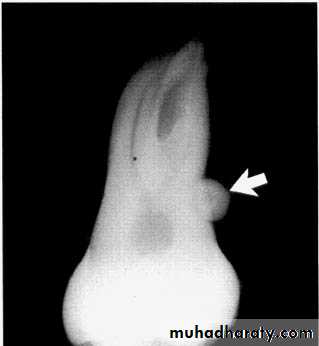

Dilaceration

*Dilaceration is a disturbance in tooth formation that produces a sharp bend or curve in the tooth (root or crown).

*CAUSES: trauma to the calcified portion of a partially formed tooth, or due to true developmental anomaly.

Dilaceration of the crown

specimenX-Ray

Dilacerated root. The apical portion of the root is bent buccally or lingually into the plane of the central ray. Note the halo in the apical region, produced by the PDL

space (arrow).